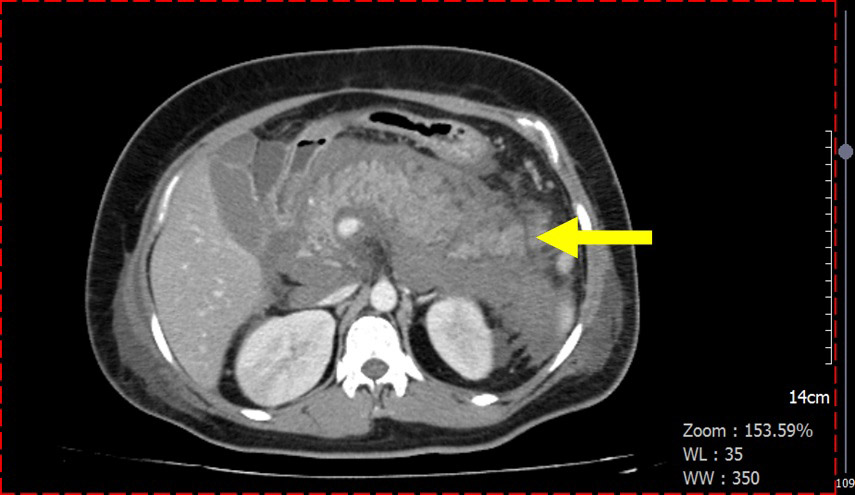

▲高三酸甘油酯導致急性胰臟炎併發後腹腔出血狀況。

陳鄭弘堯醫師進一步指出,她的胰臟急性發炎應是破表的三酸甘油酯指數肇的禍。據醫學臨床經驗,胰臟炎發作機率,若三酸甘油酯數值超過1000mg/dl就有5%風險;若超過2000 mg/dl則升高為10-20%,極可能會發生急性胰臟炎,不僅疼痛指數高,是有相當致命風險的疾病。

住院過程,該名女子病情急轉直下,因體內胰島素分泌嚴重不足而致酮酸中毒症、呼吸衰竭、血紅素下降而緊急送加護病房,確診為急性胰臟炎合併後腹腔出血。陳鄭弘堯醫師表示,急性胰臟炎的好發原因,通常與膽結石和酗酒有密切關係,但這位越南媽媽都沒有上述這兩種情形。